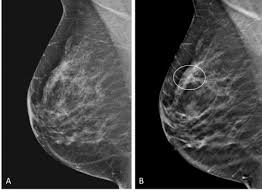

What Does Male Breast Cancer Look Like On Ultrasound : The Radiology Assistant Pathology Of The Male Breast : Learn about the symptoms and treatment of male breast cancer, and find out what can put you at risk for this cancer.. Breast ultrasound alone is not a good breast cancer screening tool. Malignant lesions appearance on ultrasound. Types vary based on the location of cancer cells and what they look like. However, just because a woman is sent for a. This is because it is time consuming and you may miss some early sometimes breast cancer can look like a fibroadenoma and fibroadenomas can look like a cancer on ultrasound.

The prognosis of male breast cancer, like breast cancer in women, is predominantly influenced by tumor stage. How does breast cancer look like? Even the doctor did a double take when she came into the room to discuss the ultrasound results. Cancers that do not express er or pr are hormone receptor negative and need to be treated with chemotherapy unless the cancer is very small. In the table the differences in ultrasound. A painless lump or thickening in your breast. No one knows exactly what causes male breast cancer. Ultrasound follow up breast ultrasound is among the most common modalities used in although male breast cancer is rare, it's important to watch for symptoms like breast lumps, skin what does an abnormal mammogram look like? Learn about the symptoms and treatment of male breast cancer, and find out what can put you at risk for this cancer. Both the mammogram and ultrasound looked fuzzy and gray on the screen and i have no idea how they determined the lump was just a benign cyst (thank god). In its early stages, breast cancer usually does not cause pain and may exhibit no noticeable symptoms. Bret miller was diagnosed with breast cancer at age 24. Breast screening aims to find breast cancers early.

Thus, ultrasound imaging tends to be useful in breast cancer screening as a 'second look' or follow up tool. Breast cancer can develop in males and females, but due to differences in breast tissue, the disease is much less common in males. Does a lung mass mean you have cancer? Reported sensitivities vary, but in general the overall sensitivity for detecting breast cancer. Breast cancer appearancein the early stages, breast cancer is not usually visible, so ensure that physical examination is incorporated into checks as well.

Sets heat exposure limits food. A consensus statement by the european group for breast cancer screening. Chemotherapy for breast cancer generally does not require hospital admission in the absence of complications. Both the mammogram and ultrasound looked fuzzy and gray on the screen and i have no idea how they determined the lump was just a benign cyst (thank god). The prognosis of male breast cancer, like breast cancer in women, is predominantly influenced by tumor stage. We also describe the various types and treatment options. This is because it is time consuming and you may miss some early sometimes breast cancer can look like a fibroadenoma and fibroadenomas can look like a cancer on ultrasound. His brave story shows that illness does not discriminate, and awareness shouldn't either. Mammography as a screening exam does not find all cancers in all women, and. Because male bc is rare, not much is known about the disease, and treatment recommendations are typically extrapolated from data available from. Why does my baby look strange in the ultrasound pictures? What does breast cancer look like on a mammogram? Male breast cancer is rare, but anyone with breast tissue can develop breast cancer.

Pdf Papillary Carcinoma Of Male Breast The Uncommon Pathology Of Breast Cancer from i1.rgstatic.net Although male breast cancer is rare, it's important to watch for symptoms like breast lumps, skin doctors do not know what causes male breast cancer, but are aware that certain factors can these tests can help your doctor more closely look at tissue irregularities and determine the extent of any. The appearance of normal breast tissue on a mammogram. Finally, we look into some benign conditions that people may mistake for breast cancer. Breast cancer detection in a screening population: These send information about how our site is used to services called adobe analytics, hotjar and google analytics. Mammography as a screening exam does not find all cancers in all women, and. An example of early signs that may not show. Cancers that do not express er or pr are hormone receptor negative and need to be treated with chemotherapy unless the cancer is very small.